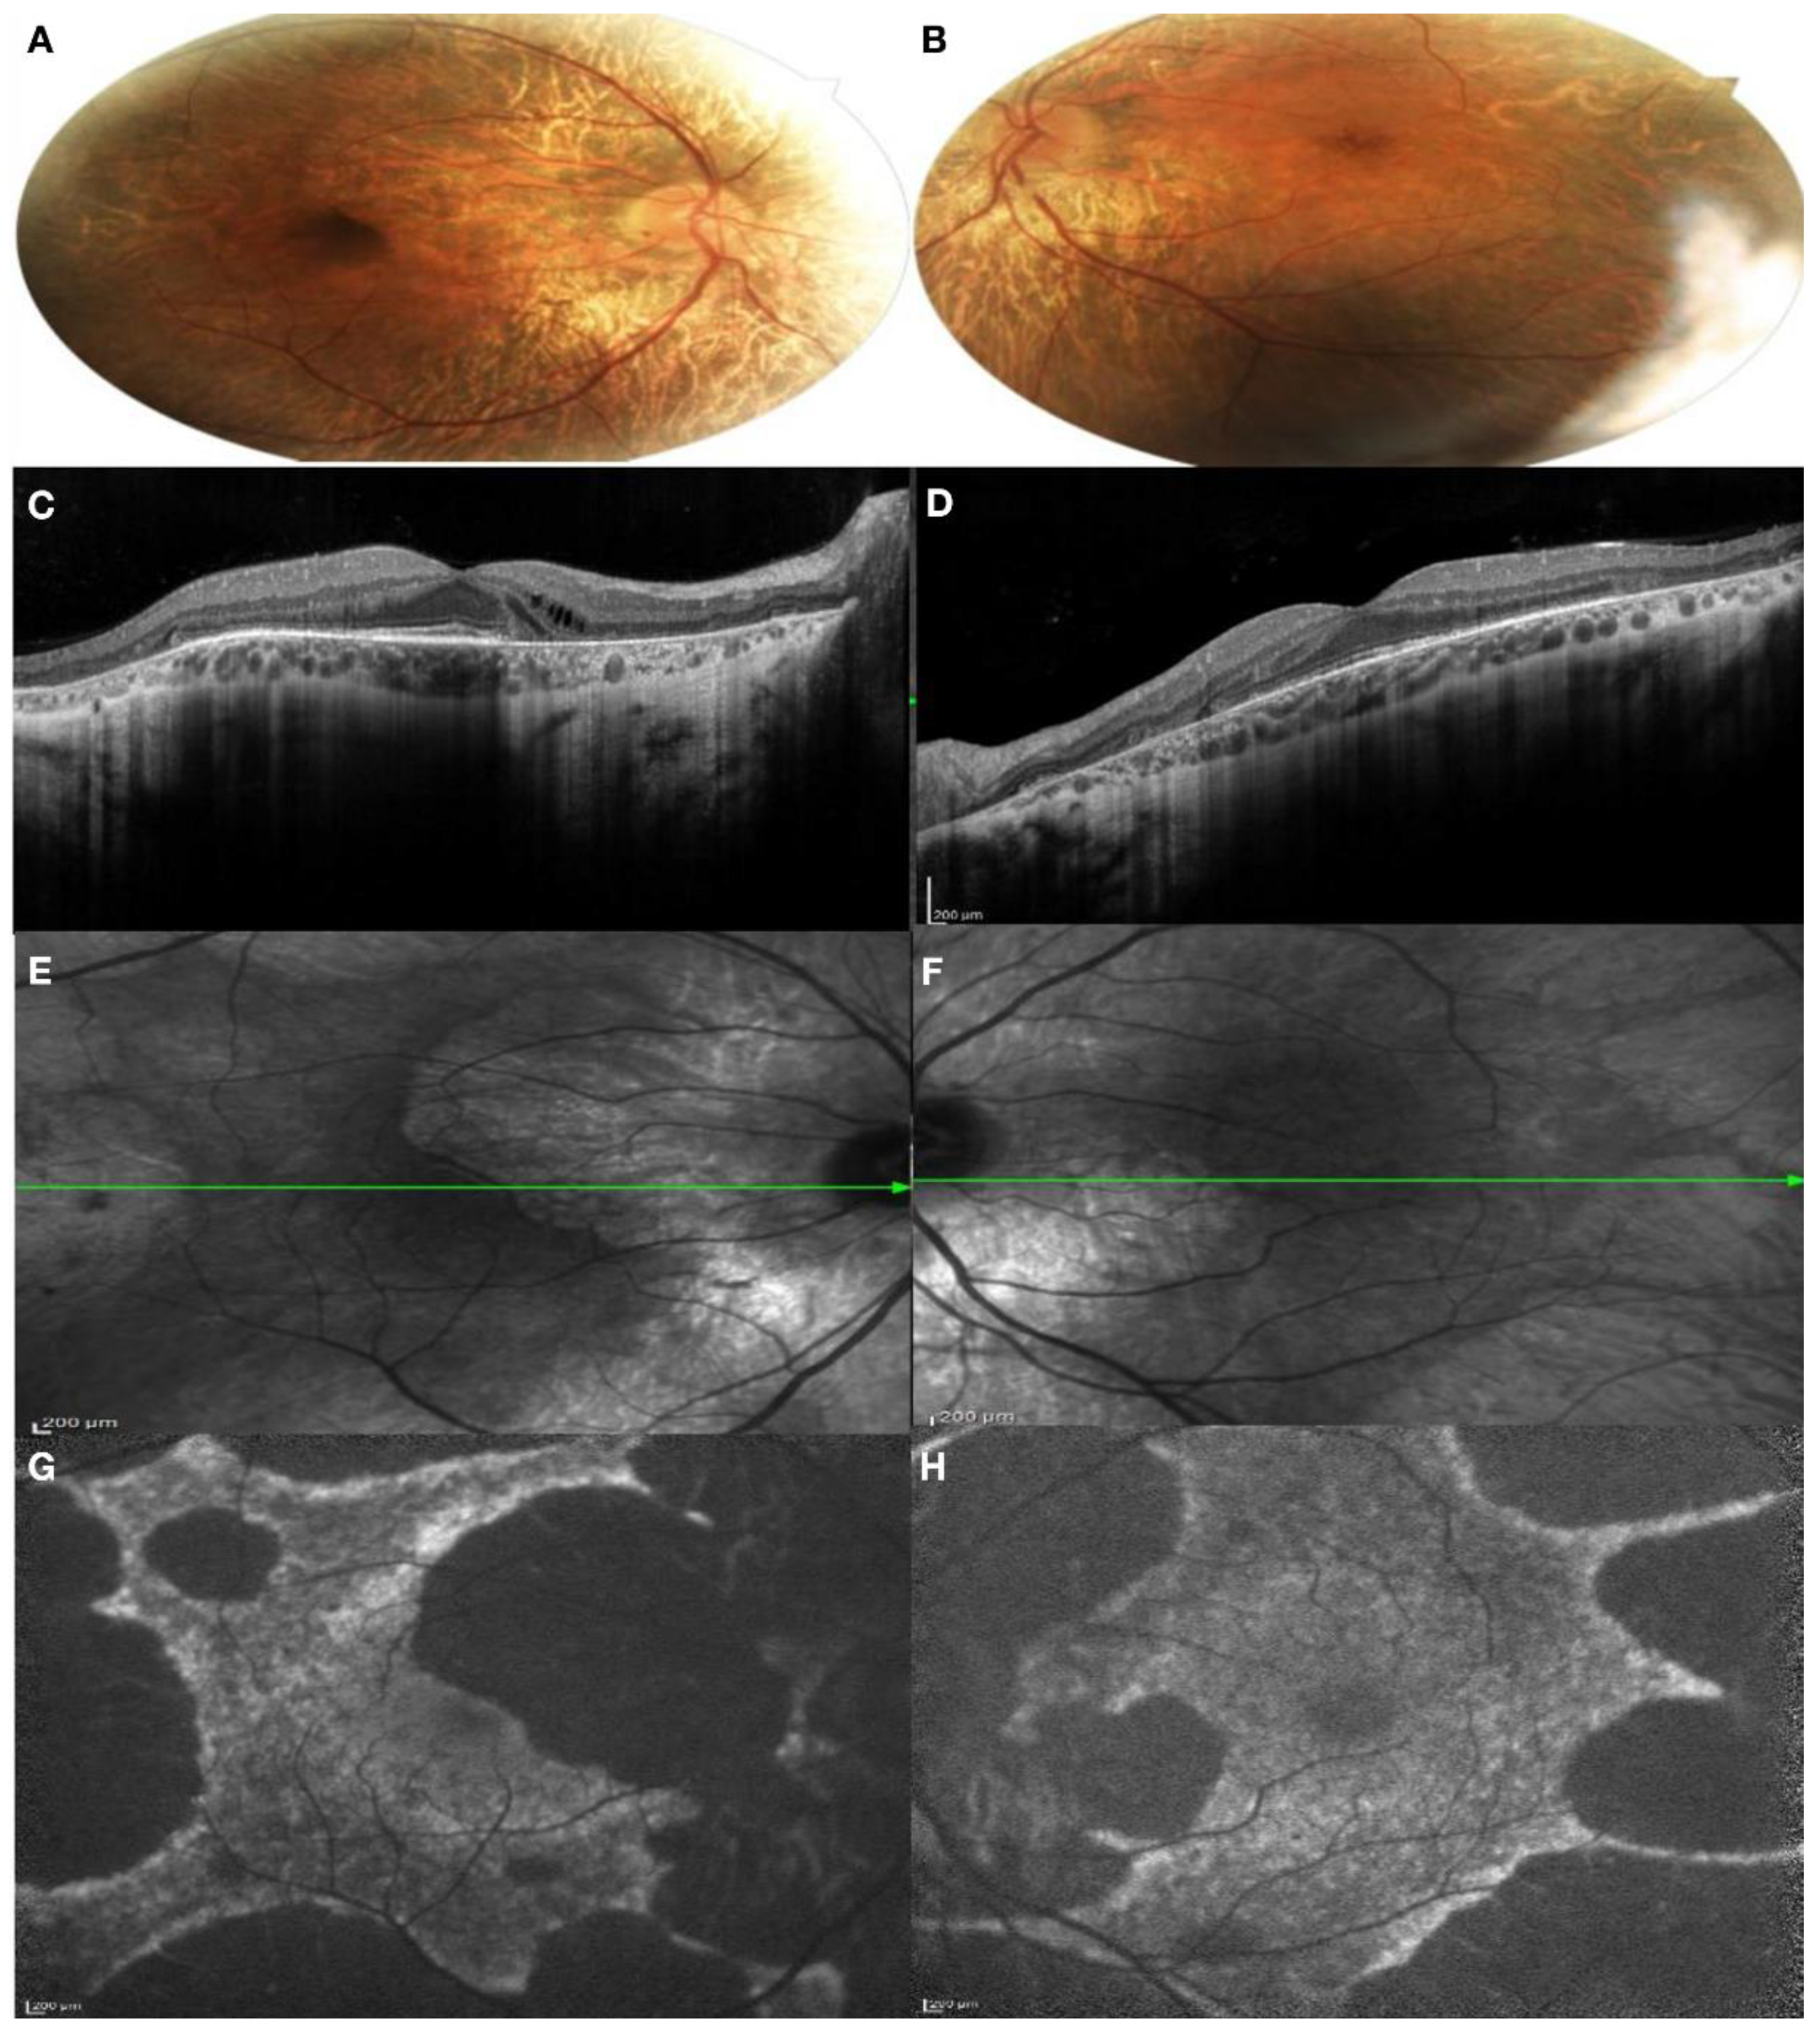

Patient I:2. The proband presented complaining of blurred vision on distance and night blindness. The patient has a moderate myopia and BCVA was 0.63 in the right eye and 1.00 in the left eye. The patient presented a severe color defect at the Ishihara test. Anterior segment examination showed a bilateral lens opacification. Fundus examination showed a large bilateral chorioretinal atrophy, large peripheral pigmentary rearrangements and focal areas of Retinal Pigment Epithelium (RPE) disruption with light sparring of central macula pigmentation, especially in the left eye (Figure 3A,B). A SD-OCT was performed, showing extensive chorioretinal atrophy and retinal thinning in the right eye with hyper-transmission posterior to the RPE, while, in the left eye, a residual central island of preserved Ellipsoid Zone (EZ) area was present, with chorioretinal atrophy in the superior area of the macula. Pseudodendritic outer retinal tubulations (ORT) were present in the context of the chorioretinal atrophy in the left eye (Figure 3C,D). Areas of residual RPE could also be visualized in Infrared Reflectance (IR) images, mostly in the left eye compared to the right eye (Figure 3E,F). FAF images in both eyes showed generalized decreased autofluorescence, with residual areas of autofluorescence in the central macular area in the right eye with a male resembling pattern and also in the temporal macular area in the left eye with a geographic pattern (Figure 3G,H).

Figure 3. Multimodal imaging of both eyes of Patient I:2. (A,B) Color fundus photography of both eyes showed a large bilateral chorioretinal atrophy; (C,D) SD-OCT of both eyes showed an extensive chorioretinal atrophy and retinal thinning in the right eye and a residual central island of preserved Ellipsoid Zone (EZ) area in the left eye; (E,F) IR images showed areas of residual RPE in the left eye; (G,H) FAF showed generalized decreased autofluorescence, with residual areas of autofluorescence in the central macular area in the right eye and also in the temporal macular area in the left eye. (A,C,E,G): right eye; (B,D,F,H): left eye.